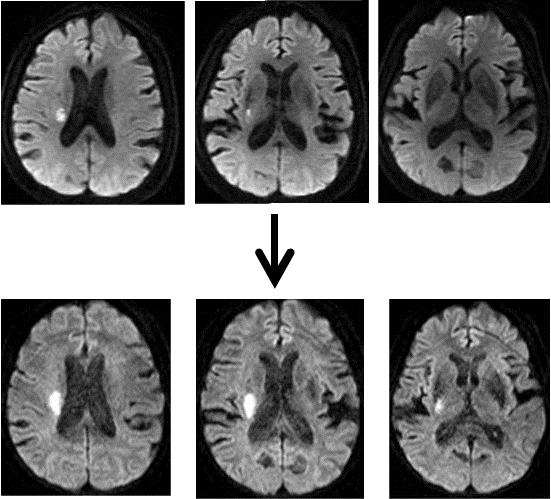

Branch atheromatous disease: 梗塞病変の拡大

上段は発症当日、下段は発症翌日の脳MRI拡散強調画像を示す。放射冠~基底核にかけての病変が拡大している。